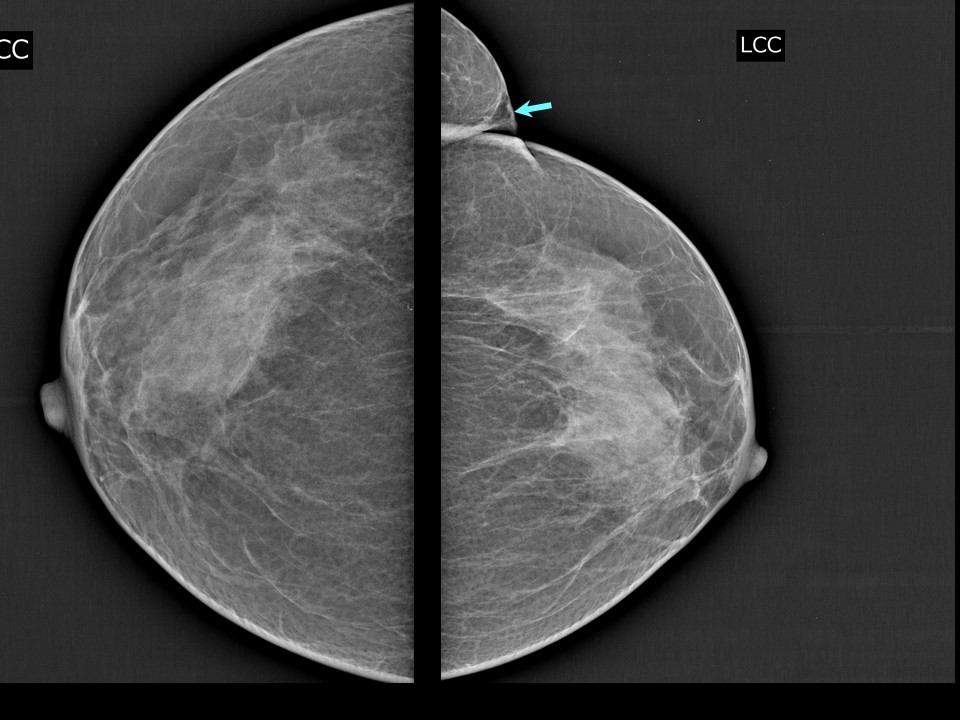

Аномалии молочной железы: медицинские примеры и визуализация

Раздел: Мудрость в деталях